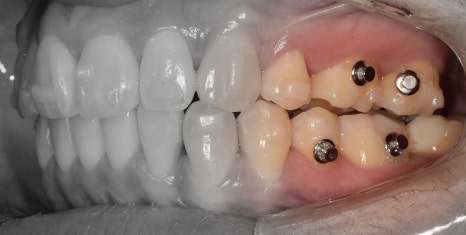

『발치 및 장치 부착, 인비절라인 진행』

표시를 해 둔, 갈고리처럼 생긴 것들은

Power arm 이라는 것들입니다.

이는, 치아들을 계획 했던 대로 정확히

이동을 시키게끔하는 보조수단으로 쓰입니다.

이후, 발치 공간이 조금씩 거의 다 폐쇄되면서

인비절라인 실버버튼을 부착시킵니다.

이것 또한, 보조도구입니다.

치열 전체를 덮는 인비절라인과 같이 맞물려서

정확한 치아의 위치 이동을 돕는 역할입니다.